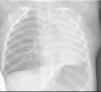

A las 24h permanece asintomático, con resolución completa de la atelectasia (fig. 3), por lo que se decide alta a domicilio con tratamiento antiasmático, sin presentar recidivas.